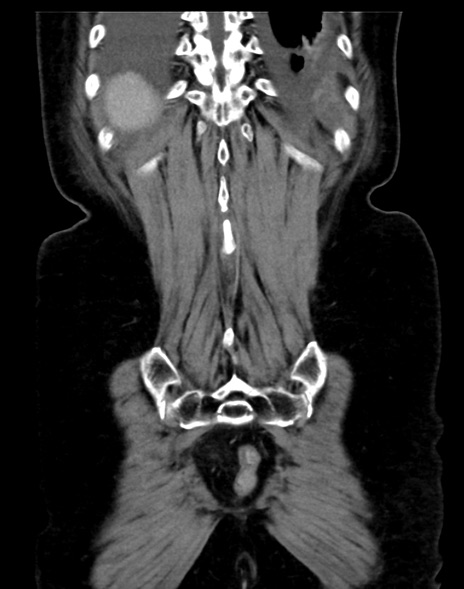

症例13 CT(冠状断像)1日半後